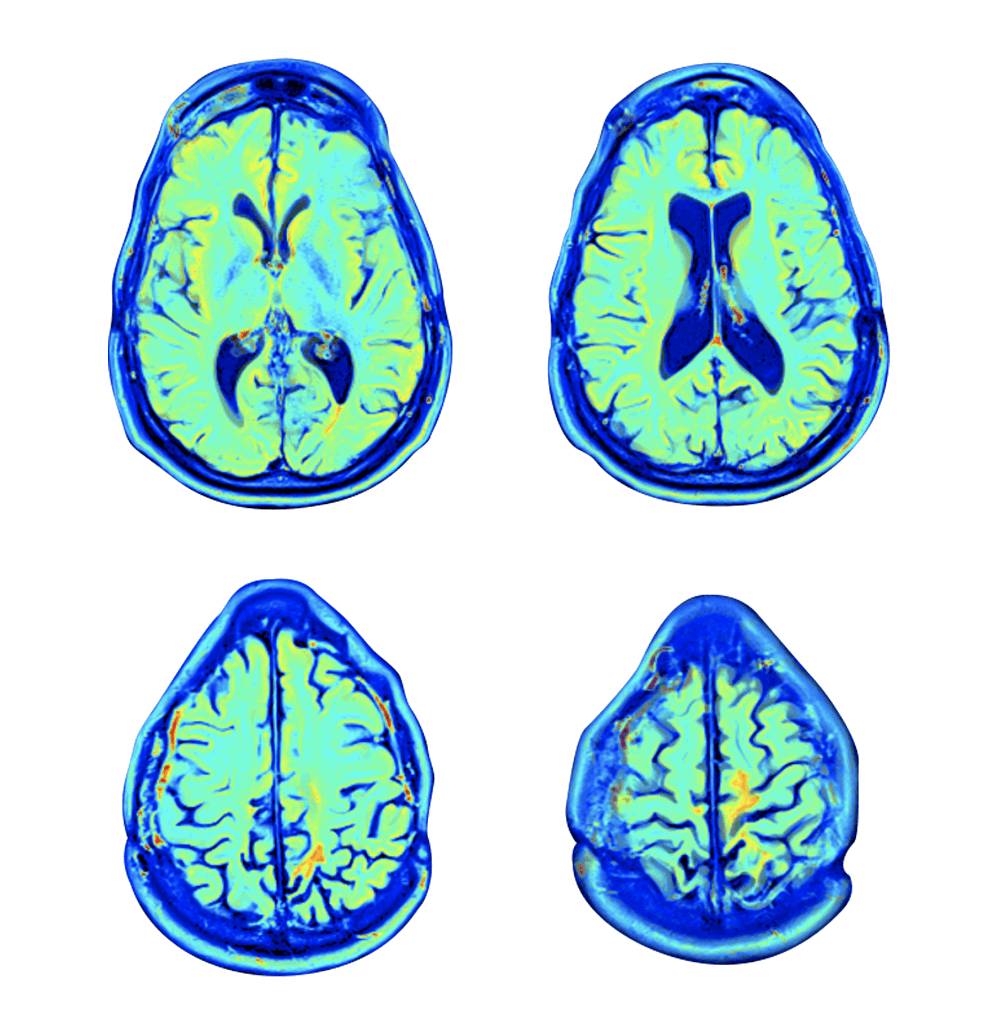

تقييم طبي وفسيولوجي وذهني شامل على مدار ثلاثة أيام يقوم به طاقم مركز التميّز الذهني والبدني الطبي المعتمد، والذي يضم نخبة من الأطباء، وخبراء علم النفس العصبي، والمعالجين الفيزيائيين، وأخصائيي علم وظائف الأعضاء، وفريق التمريض. ويشمل ذلك أكثر اختبارات تصوير الدماغ تطوراً بما يتناسب مع احتياجاتك – مثل التصوير بالرنين المغناطيسي لتروية الدماغ MRI، والتصوير بالرنين المغناطيسي الوظيفي fMRI، والتصوير المقطعي المحوسب بفوتون واحد SPECT.

قامت الدراسات السريرية الحديثة في مركز شامير الطبي بقياس آثار العلاج بالأكسجين عالي الضغط HBOT على المرضى الذين يعانون من قصور عصبي، على سبيل المثال، الفقدان الخفيف للذاكرة، أو ردود الفعل الضعيفة نتيجة إصابات رضحية خفيفة في الدماغ.